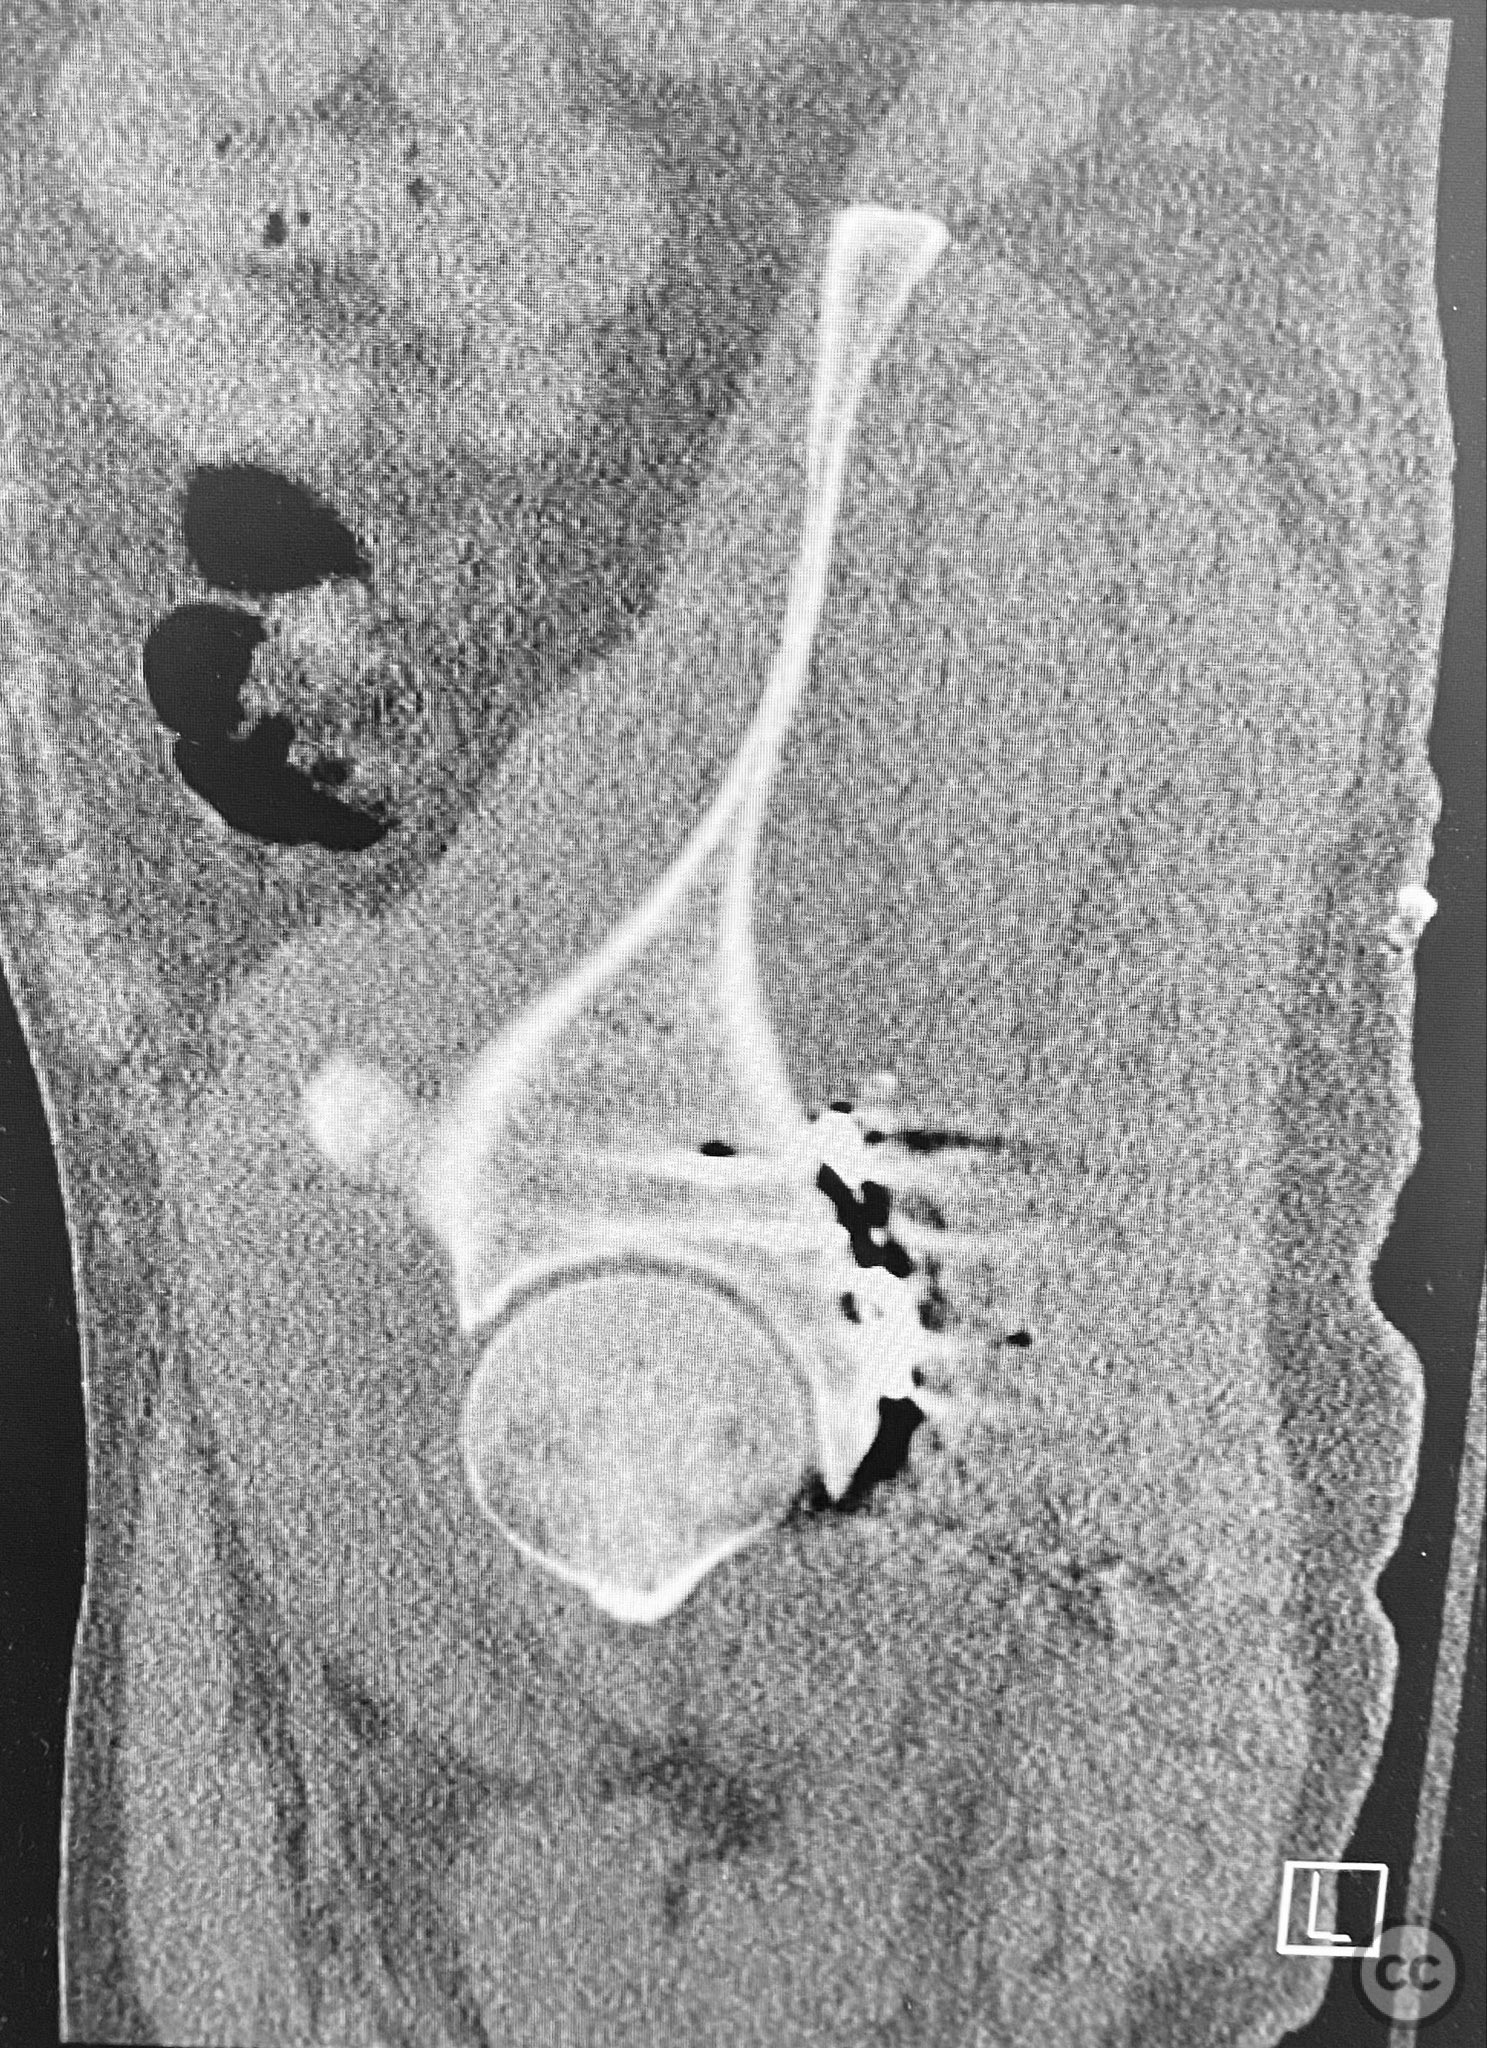

Clinical and radiological findings:  A patient presented with a seemingly non-comminuted, wide, and long posterior wall (PW) acetabular fracture fragment. Axial computed tomography (CT) images demonstrated the thickness of the PW fragment, the articular surface, and multiple areas of subchondral impaction. Preoperative planning identified the size, location, and depth of the impaction zones, as well as an essentially nondisplaced transverse acetabular fracture line, which was not readily apparent on initial imaging. No significant displacement of the transverse component was noted. The AO/OTA classification is 62-B1.3 (posterior wall and transverse acetabular fracture).

Intraoperatively, elevation and reduction of impacted articular fragments were performed, followed by bone grafting of subchondral defects. The posterior wall fragment was anatomically reduced and initially stabilized with a contoured plate. Intraoperative fluoroscopy (obturator oblique view) was utilized to guide placement of an additional screw through the plate above the joint, traversing both the posterior wall fragment and stabilizing the transverse fracture line. A supplementary medial plate was applied to further support both fracture components. Postoperative CT imaging confirmed satisfactory reduction of both the posterior wall and transverse fractures, as well as restoration of articular congruity in previously impacted areas. Consideration is given to whether initial reduction and lag screw fixation of the transverse component prior to plate application may have improved reduction; however, final imaging demonstrated acceptable alignment.